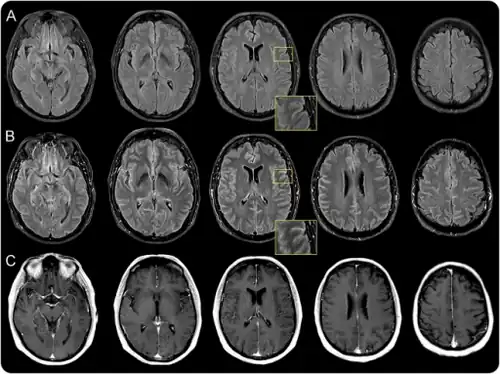

| Viral meningitis causes inflammation of the meninges. | |